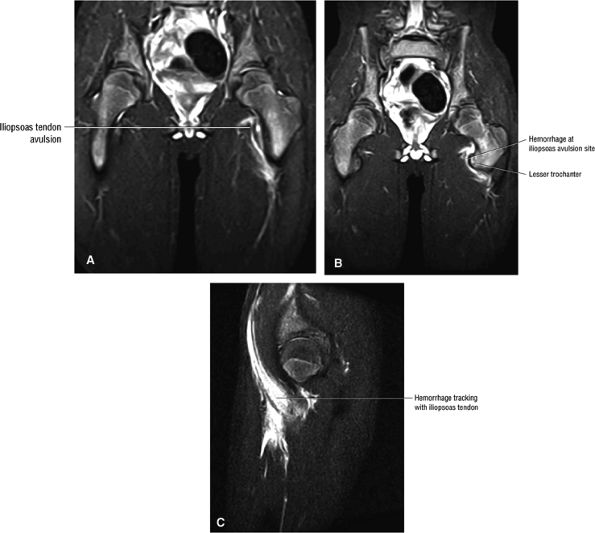

FIGURE 3.2 ● PSOAS MAJOR The psoas major flexes the femur (thigh) and vertebral spine on the pelvis when the leg is fixed. The psoas major and iliacus form the iliopsoas muscle group. Iliopsoas muscle tendon strain is the result of forceful contraction of the iliopsoas when the thigh is fixed or in the extended position.